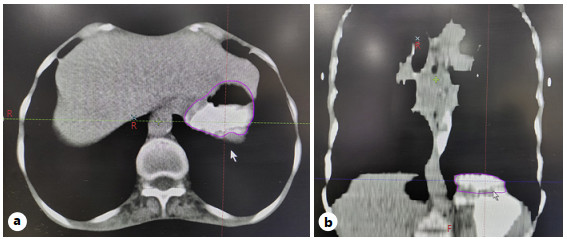

Materials and Methods: A retrospective analysis was performed of 27 patients with EC who underwent NACRT followed by esophagectomy with cervical esophagogastric anastomosis between January 2015 and July 2018. The GF was retrospectively contoured; dose-volume parameters of the GF were recorded. Postoperative AL was identified from surgical records. Logistic regression analysis was used to identify risk factors associated with AL.